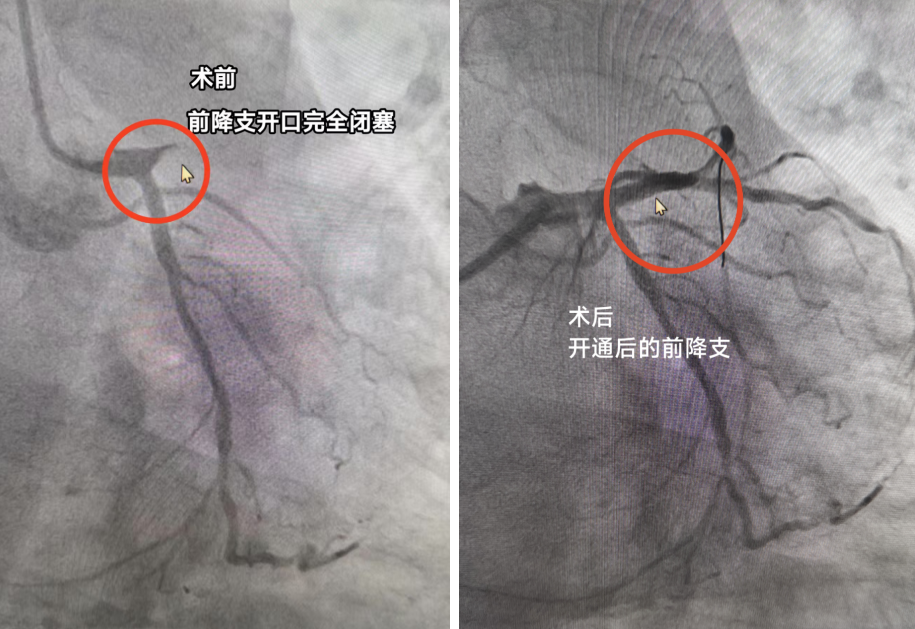

手术组:在患者身体因按压不断晃动的极端困难下,凭借精湛技术和强大心理素质,消毒、穿刺、置管、造影。前降支开口完全闭塞!从穿刺开始到导丝通过病变处仅仅只用了15分钟,导丝成功通过闭塞段后,球囊扩张、血栓抽吸、支架植入等堵塞血管成功开通!血流恢复灌注心肌。患者心律逐渐稳定,血压回升,生命体征转平稳。